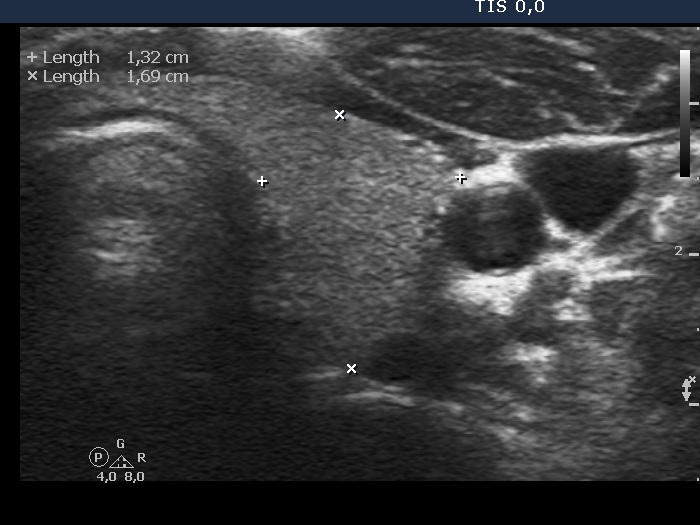

Subacute granulomatous thyroiditis - case 264 (ultrasonographic picture 3)

Right lobe, longitudinal scan